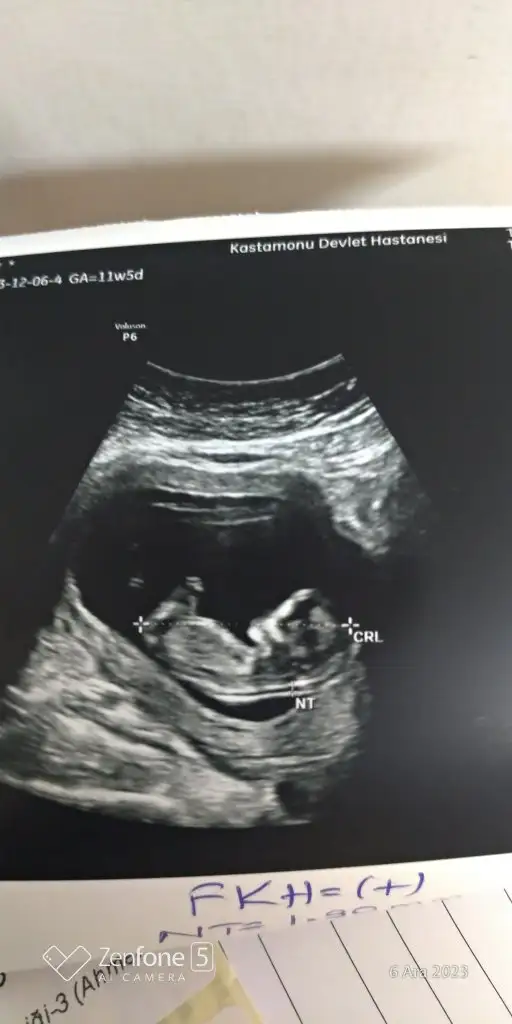

Merhaba lar hanımlar ilk 2 resim 11 haftalikken diğer resimlerde 15 haftalikken banada tahminde bulunurmusunuz